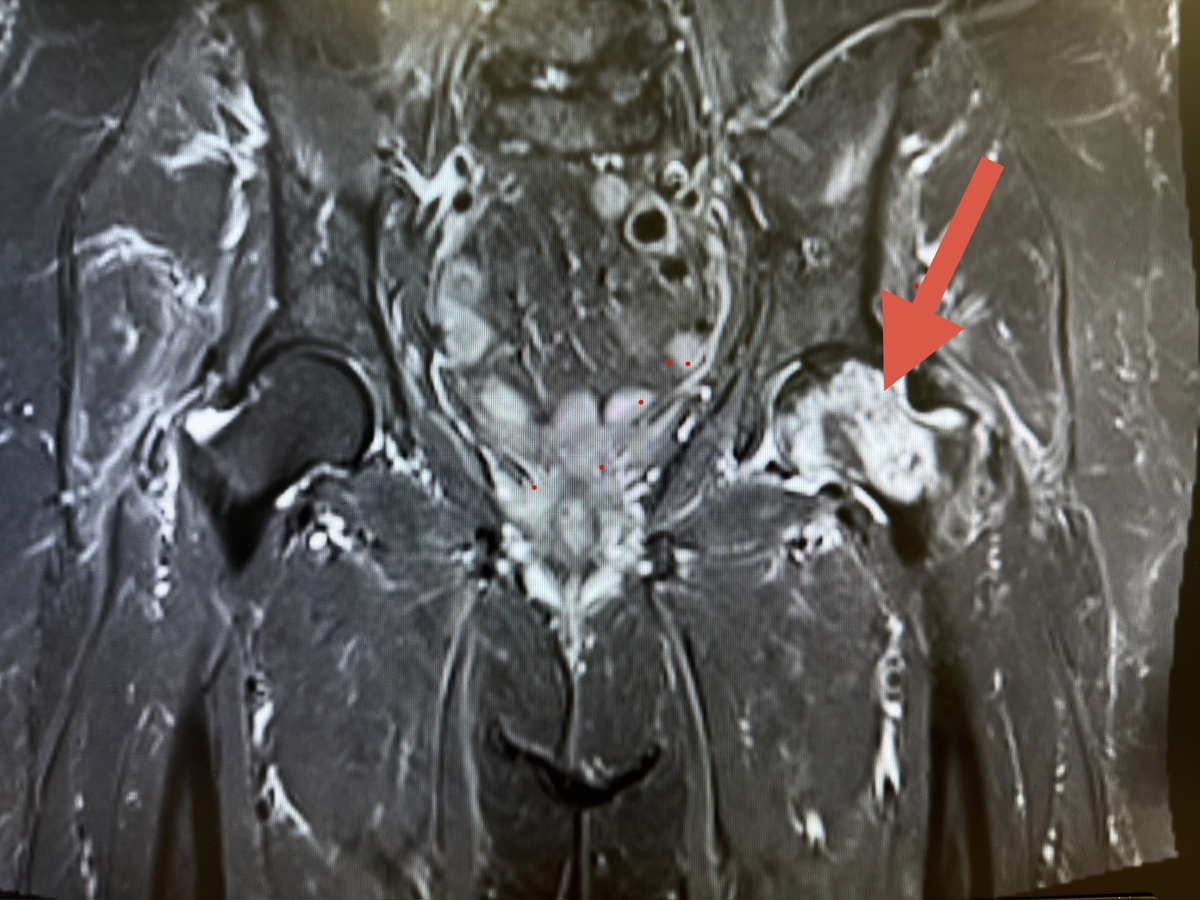

Возвращаясь к пациентке, чей рентген я показал вверху. Первое же МРТ - и диагноз ясен и очевиден: асептический (он же - аваскулярный) некроз головки левой бедренной кости.

Опять же: не нужно быть специалистом, чтоы увидеть, как сильно изменена структура головки левого бедра (стрелка). Справа, в отличие от левого, кость совершенно нормальная.